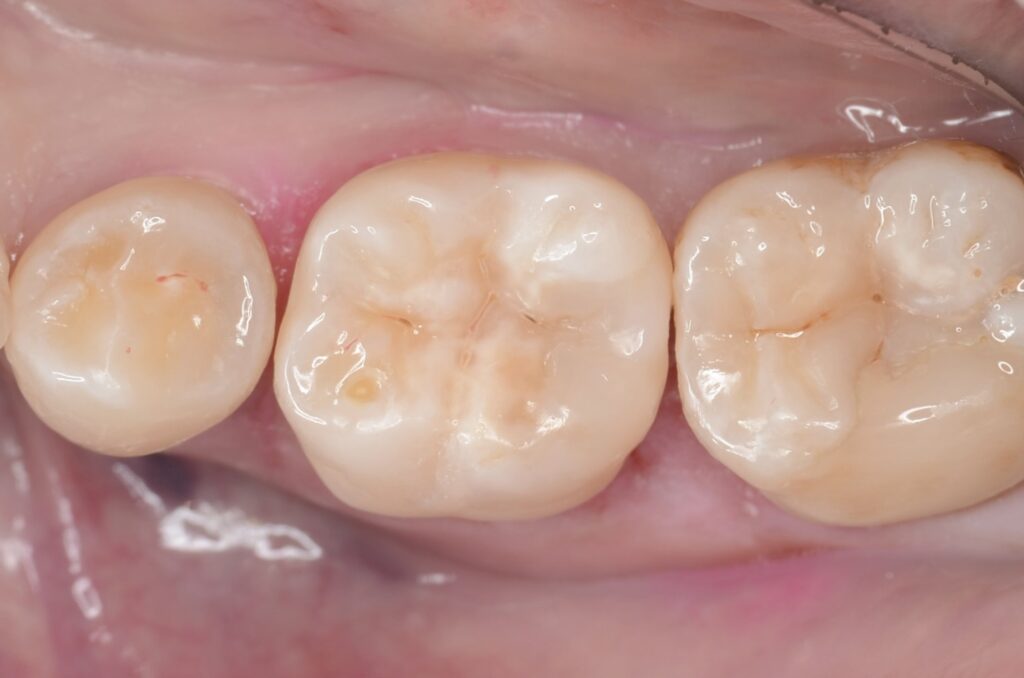

神経を取りたくない・MTAセメント・歯髄保存療法虫歯の治療・ダイレクトボンディング

30代 虫歯治療 VPT(歯髄温存療法)ダイレクトボンディング #66

02虫歯治療(ダイレクトボンディング)

ダイレクトボンディングは、歯の欠損や小さな虫歯を即座に修復する方法です。歯と同色の材料を直接歯に盛り付け、自然な見た目と機能を取り戻します。

1本の歯は、一生の間にわずか5回しか治療に耐えられないと言われています。すなわち5回以上治療すれば抜歯に近づくのです。

だからこそ、虫歯にしない。

万が一虫歯になってしまったら、できるだけ早めに治療する。

最小限に削って、精密に治す。隙間があれば、そこから虫歯になるから。

決して裸眼で治療はできません。それが、私たちが拡大視野で丁寧な治療にこだわる理由です。